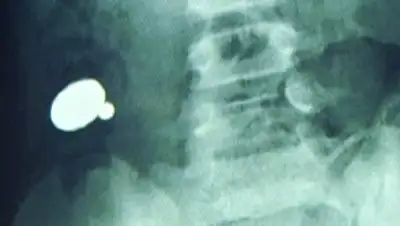

В семье Лаврентьевых из Норильска до сих пор не могут оправиться от горя. Когда у двухлетнего Алеши заболел живот, взрослые подумали, что это отравление. Врачи поставили диагноз «гастрит». А когда ребенок впал в кому, срочно сделали рентген и на снимке увидели, что в желудке малыша с десяток металлических шариков, но было поздно. Алеша умер сразу после операции. После смерти ребенка в Следственном комитете тогда начали проверку. Экспертиза показала, что трагедия произошла именно из-за игрушки.